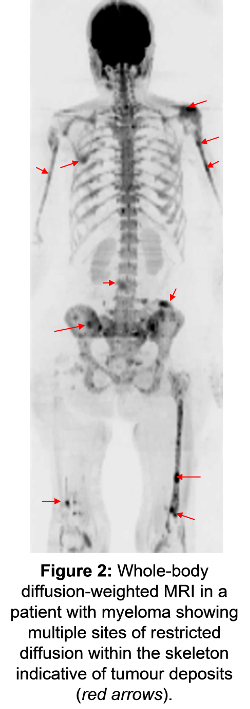

Another good human model system is where multiple sites of secondary tumour exist throughout the body (see Figure 2). Some progress quickly, some less so and some remain stable over long periods.

New whole-body techniques with MRI and PET and the ability to fuse these datasets is allowing us to unravel the metabolic, cellular and vascular features of a tumour and its environment. We can then link these features to variations in disease progression and the development of resistance to treatment.

Diffusion-weighted MRI, which characterises the water diffusion properties within tissue and so reflects cell density and matrix properties, is proving to be a particularly valuable prognostic marker in a variety of cancer types.

Tissue properties such as water diffusion within solid tumours are a surrogate for the density of cell packing and the properties of the extracellular matrix. That means that more restricted diffusion can indicate more aggressive disease. Tumours are also classically hard and tissue stiffness can be quantified using elastography both with ultrasound and MRI.